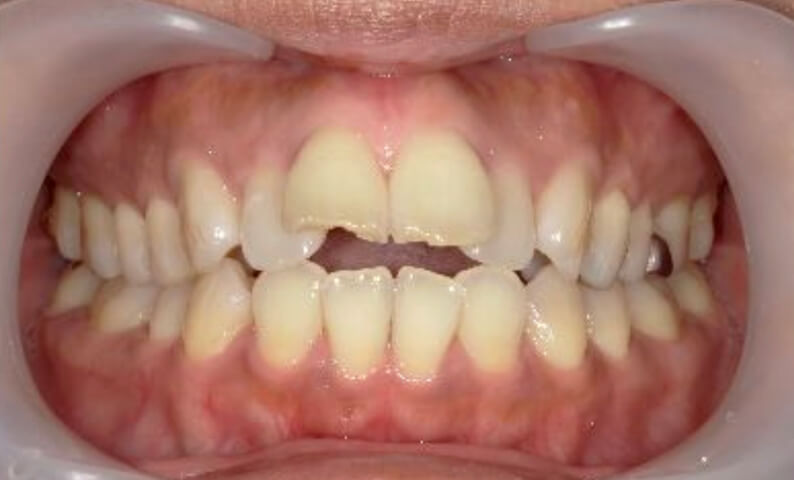

症例_003 上下顎の部分矯正

治療期間:12ヶ月金額:54万円+税男性八重歯前歯のガタガタ

| Before | After |